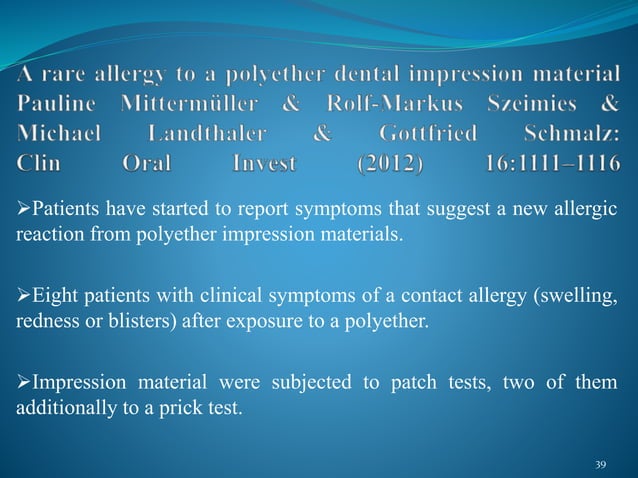

Clinical Characteristics Of An Allergic Reaction To A Polyether Denta…

allergic reaction impression polyether clinical

Clinical Characteristics Of An Allergic Reaction To A Polyether Dental

impression polyether allergic reaction mucosa preoperative

Clinical Characteristics Of An Allergic Reaction To A Polyether Dental

Clinical Characteristics Of An Allergic Reaction To A Polyether Dental

Clinical Characteristics Of An Allergic Reaction To A Polyether Dental

Clinical Characteristics Of An Allergic Reaction To A Polyether Denta…

allergic dental characteristics polyether clinical

Clinical Characteristics Of An Allergic Reaction To A Polyether Dental

material allergic reaction

Clinical Characteristics Of An Allergic Reaction To A Polyether Dental

Clinical characteristics of an allergic reaction to a polyether dental. Clinical characteristics of an allergic reaction to a polyether dental. Clinical characteristics of an allergic reaction to a polyether dental